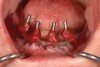

Fig 18. The patient’s intraoral condition.

Figure 18

Dental rehabilitation with the All-on-4 treatment concept is often a life-changing event for edentulous and terminal dentition patients that results in unprecedented quality of life improvements (Figure 17 through Figure 20).